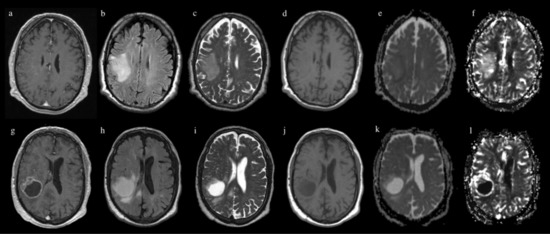

2. Materials and Methods